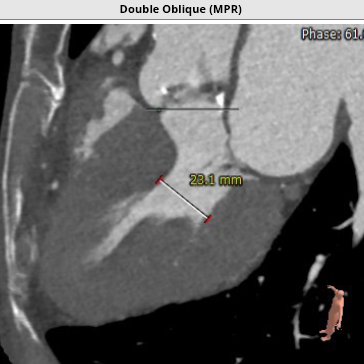

超声心动图显示,主动脉最大流速482cm/s,最大压差93mmHg,平均压差50mmHg,LVEF65%。CT显示主动脉瓣为TYPE2型二叶瓣,严重钙化,右无、左无可见粘连伴钙化,瓣环平面可见钙化,钙化延伸至流出道及二尖瓣前叶根部,左冠高度约12mm,瓣叶长度14.9mm,存在一定左冠风险,法式窦平均直径33.7mm,STJ高度约21.8mm、直径约30.2mm。

主动脉弓部走行较平缓,弓顶部可见少许钙化,主动脉弓部三根毛开口未见明显狭窄征象、未见发育变异,胸主动脉、腹主动脉走行较平直、腹主动脉多发严重钙化斑块,管腔未见明显狭窄,双侧髂动脉-股动脉走形迂曲,双侧髂动脉多发严重钙化斑块,部分呈半环形、马蹄形分布,右侧股动脉可尝试做为主入路,左股动脉作为脑保护入路。虚拟瓣环直径25mm,左室流出道平均直径23.3mm,拟植入VenusA Plus 23/26号的瓣膜。术中balloon sizing确认瓣膜型号,同时确认冠脉风险。